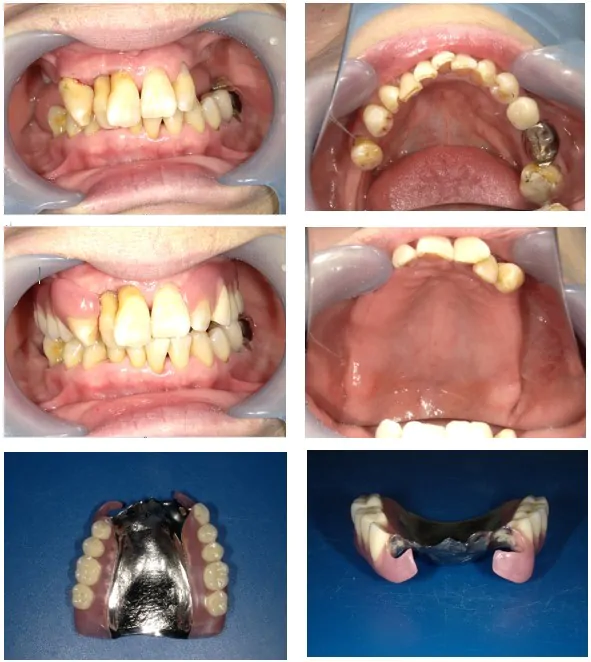

歯ぐきが腫れて痛いというのが来院のきっかけでしたが、それ以外にも使用していた入れ歯の調子も悪く、全体的な治療が必要な状態でした。入れ歯は、他の歯科医院で2年ほど前に入れていたものがありましが、違和感が強く、結果的に殆ど外していたそうです。入れ歯を外していることで、奥歯では噛み合わせることが出来ないため、その力は自ずと前歯にかかってきます。下の前歯によって、上の歯を突き上げる形となり、結果的に他の歯や、今回の急性症状をおこしていた歯周病が悪化する危険性がありました。奥歯でしっかり噛める義歯(入れ歯)を入れない限り解決しないことがわかります。

歯周病が悪化して歯を支える歯槽骨まで影響が出ていた歯は、やむを得ず抜歯をして、そこへ即時義歯をセットしました。即時義歯とは、抜いたその日にすぐに使うことができる仮の入れ歯を入れる治療法です。本来は、歯を抜いた後に型取りをして、技工所に製作してもらいますので、どうしても歯がない期間が出てしまいます。即時義歯は、歯を抜く前に「抜けた後はこういう状態になることを予想して先に入れ歯を製作しておく」方法になります。保険診療の義歯の場合、制度上の6か月は新しい入れ歯が作れないルールになっているため、今回は自費診療の義歯として、できるだけ精度も高い義歯製作に臨みました。並行して歯周病治療を進め、歯ぐきの状態が落ち着いたところで、本格的な義歯製作に入りました。歯周病治療の結果、どこまで歯が残せるか、長期的にもつ歯と残念ながらそうではない歯をシミュレーションして、将来を見通すことが入れ歯作りには大切な要素です。それにより設計が変わってきます。

今あるご自身の歯を前提に入れ歯は製作しますが、将来抜けてしまう可能性が高い歯がある場合は、そこを増歯(人工歯を付け足す修理)できるように設計するなど、多少の口腔内の変化にも対応できる入れ歯を設計します。そうしないと、また一から再生し直すことになり、身体の負荷、時間や経済的な負担もしいてしまうことになります。今回は上顎で吸着性を得るため少し大きめの「床」が必要な形状でしたので、軽くて丈夫なチタン素材のものを選択しました。現在は、「よく食べられるようになった」と喜んで頂いています